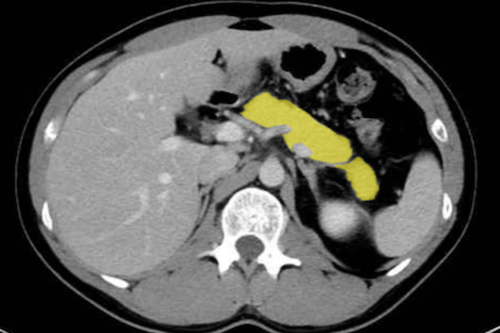

췌장

- 췌장염

- 급성 췌장염(부종형·괴사형) 및 합병증: 가성낭종, 출혈, 종격동 누공

- 만성 췌장염: 석회화, 위축, 담도 협착

- 췌장 종양

- 췌장암(PDAC) 혈관 침윤·전이 평가

- 신경내분비종양(NET)·IPMN·MCN·SPN